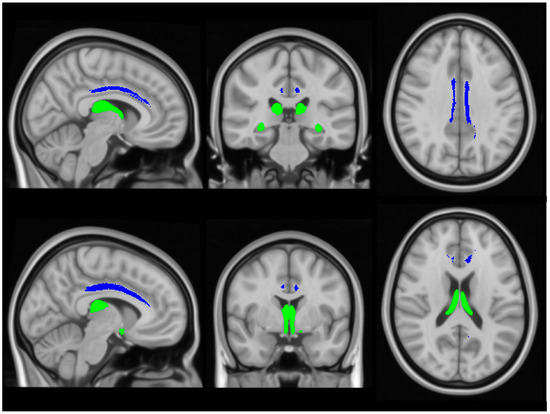

Input raw diffusion tensor imaging data were pre-processed using tools of the FMRIB’s software library (FSL) (https://fsl.fmrib.ox.ac.uk/fsl/docs/#/ accessed on 5 July 2024). DTI data were eddy current-corrected, skull stripped, and a tensor model was fitted to create fractional anisotropy (FA), axial diffusivity (AD) and radial diffusivity (RD) mpas. FSL’s tract-based statistics (TBSS) module was then utilised for non-linear registration, skeletonisation and the creation of a mean FA mask. Each participant’s individual FA, AD and RD images were then merged into 4-dimentional (4D) AD, FA and RD image files. Diffusivity metrics were retrieved from the four (AD, FA, RD) concatenated diffusivity files using the FMRIB fornix label [64] and the cingulum labels of the ICBM-DTI-81 white-matter atlas [65] in the two hemispheres separately (Figure 3). The Fornix_FMRIB_FA1mm template [64] is derived from probabilistic tractography pathways of the fornix in 49 adults registered to FMRIB58_FA standard-space and averaged [64].

Figure 3. The assessment of white matter integrity in the fornix (green) and cingulum (blue), based on diffusivity measures.